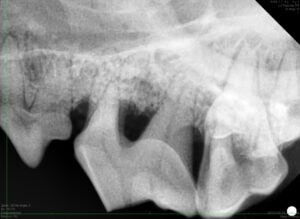

さらに歯科レントゲンを撮影すると、顎の骨が溶けているが分かりました。

左側:抜歯

当初は歯内治療をご希望でしたが、破折に加えて歯周組織が大きく失われていたため、歯を温存するには歯周組織再生治療が必要になります。

今回は飼主さんと相談の上抜歯となりました。